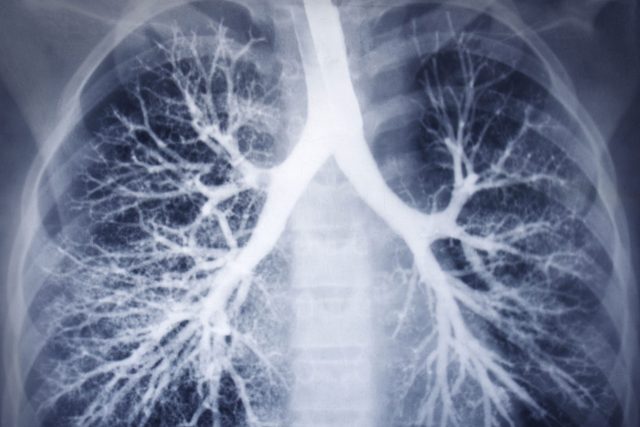

Bez dýchání nedokážeme žít. Pokud se nám vzduchu nedostává jen několik minut, nastane mozková smrt. Proto je důležité chránit si orgány, které se na dýchání podílejí. Jaké nemoci plic nás mohou ohrožovat na životě?

Zápal plic

O co jde: Tato zánětlivá nemoc postihuje zejména plicní sklípky. Často začíná jako zánět horních cest dýchacích a později se rozšíří i do dolních cest.

Plíce se naplní tekutinou, dojde k uzávěru plicních sklípků a zablokování volného přístupu kyslíku do krve.